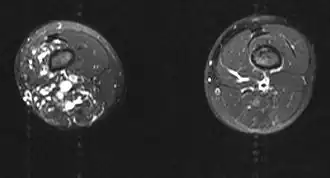

| Imagem por ressonância magnética | |